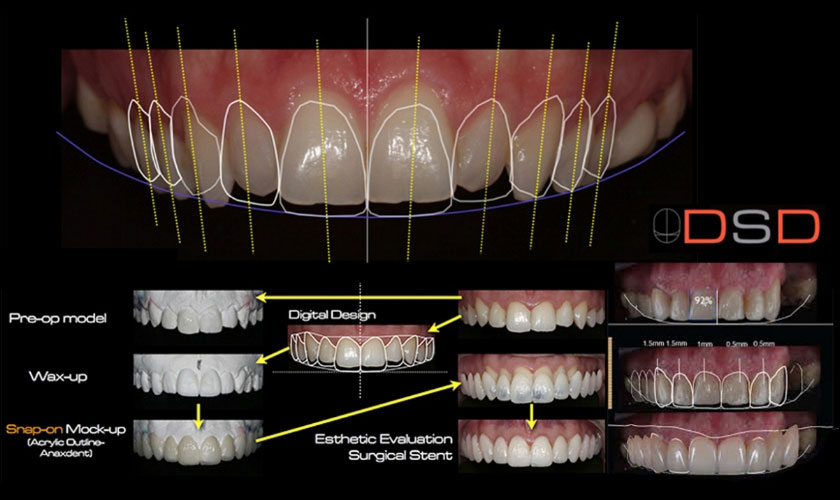

Thiết kế nụ cười cho thấy trước được kết quả trước khi thực hiện điều trị

QUY TRÌNH ĐIỀU TRỊ CHO KHÁCH HÀNG DỰA TRÊN THIẾT KẾ NỤ CƯỜI

- Lên giá khớp: đánh giá khớp cắn của bệnh nhân rồi điều chỉnh những cản trở trên miệng của bệnh nhân

- Tạo mẫu sáp chẩn đoán (Wax-up): thực hiện mẫu Wax-up theo kích thước đã được thực hiện trên Smile Design

- Chỉnh hình nướu: điều chỉnh nướu sao cho đường viền nướu các răng đều đặn, cân xứng

- Mài cùi: bác sĩ tiến hành mài cùi, lấy dấu răng để gửi cho Labo làm răng sứ

- Làm răng tạm: làm răng tạm từ mẫu Wax-up đã thực hiện trên giá khớp

- Hoàn tất: gắn răng sứ cho bệnh nhân, hoàn tất điều trị